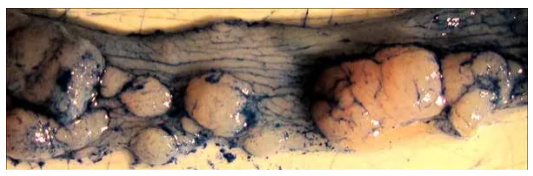

3. 處死后取小鼠結(jié)腸,可觀察形成的腫瘤。值得注意的是,末端結(jié)腸/直腸腫瘤負(fù)荷較高(左上圖),近端結(jié)腸腫瘤呈現(xiàn)褶皺狀紋理(右上圖),腫

瘤負(fù)荷很少。近距離觀察末端結(jié)腸可觀察到許多不同大小的腫瘤(下圖)。

image.png